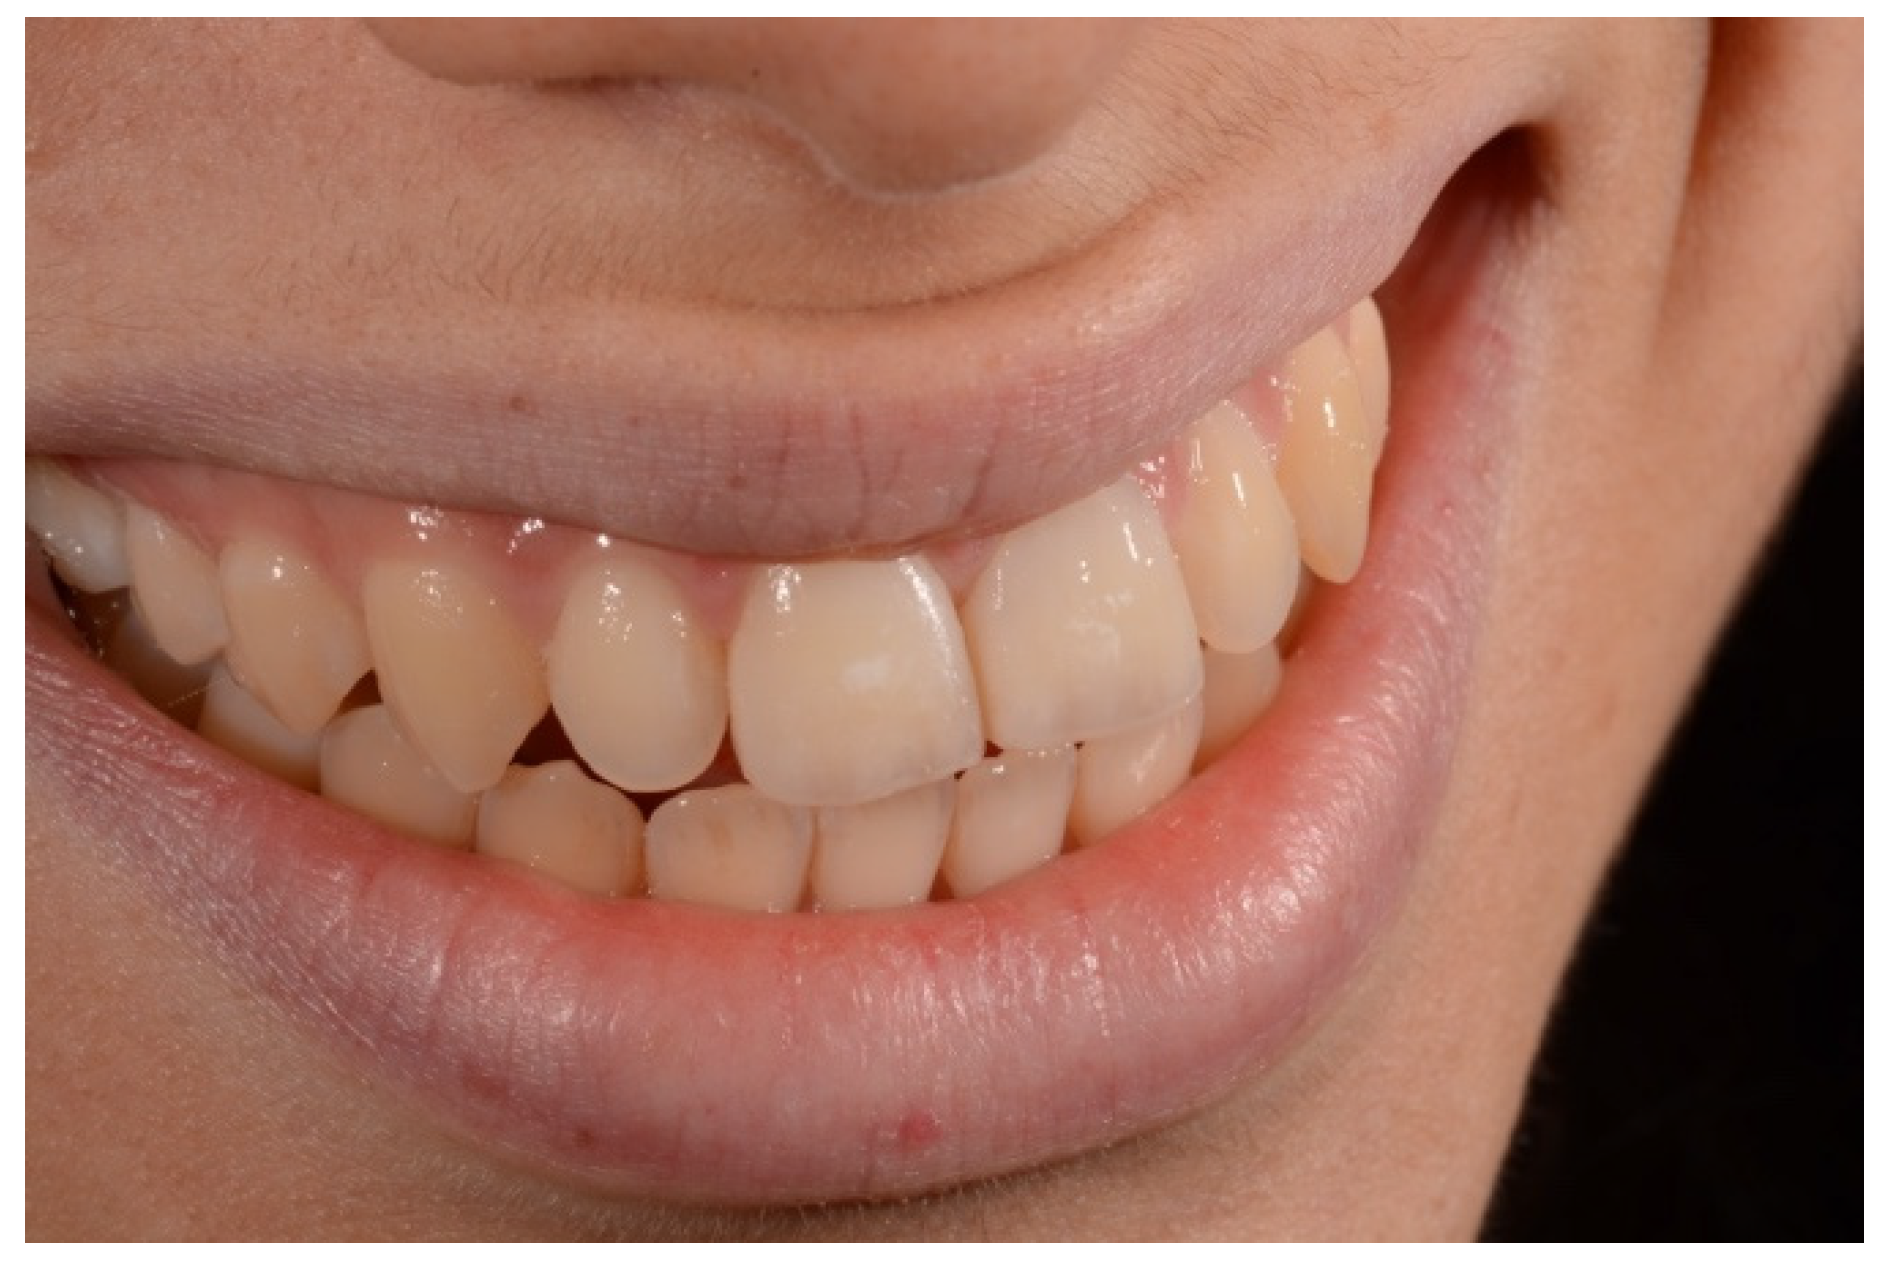

2. Case Presentation

- Molding palatal wall and incisal margin;

- Building interproximal walls with matrices;

- Layering free-hand buccal surface.